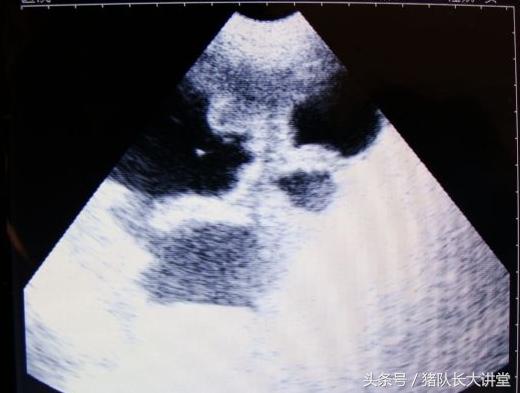

27天图

A、可以较为准确的测出是不是有小猪,具体使用办法,根据说明使用,大家也可以提出问题;关注,一般你检测有的就是有了,单是检测没有的时候应该多视察;

中间的黑球是初期胚胎